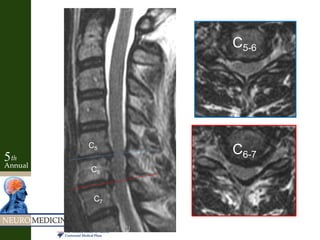

C5-6

C6-7

C5

C6

C7

Case Example • 64yo female with diffuse neck pain – Radiates bilateral arms • No weakness or numbness • Slightly hyperactive reflexes • Negative Spurling’s

Key Factors • Neckpain and “radiculopathy” into arms • Interscapular pain – Cloward 1959- Disc herniations of lower cervical levels induced spasms of para-scapular muscles • Motor/sensory exam not localizing • Myelopathic with hyperactive reflexes • Negative Spurling’s • Positive discogram – Reproduced pain at levels and no pain at adjacent levels • Concordant MRI